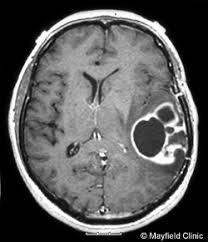

Diagnosis based on symptoms and physical examination. X-ray skull and brain had only a modest description of a brain tumor. All types of brain tumors can usually be seen on CT scan or MRI, which could also determine the size and location of which is uncertain. Pituitary tumors are usually found if it had hit the nerve of sight. Blood tests showed abnormal hormone levels and pituitary tumors can usually be diagnosed by CT scan or MRI. Biopsy is performed to determine the type and nature of tumors (malignant or benign). Sometimes microscopic examination of cerebrospinal fluid obtained by lumbar puncture, can show the existence of cancer cells. If there is increased pressure inside the skull, the lumbar puncture can not be done due to pressure changes suddenly could cause herniation. In the herniation, increased pressure within the skull pushing down the brain tissue through a narrow hole at the base of the skull, so that pressing the lower part of the brain (brainstem). As a result, functions that are controlled by the brain stem (breathing, heart rate and blood pressure) will experience interference. If not addressed, herniation can cause coma and death.